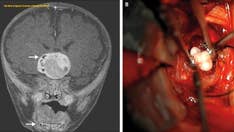

Doctors at Mount Sinai in New York, who cut into a 42-year-old woman’s brain last September to remove a suspected malignant tumor, were reportedly baffled when they found a mass resembling a “quail’s egg."

After doctors removed the mass from Rachel Palma's brain they cut it open and placed it under a microscope. They realized it was a tapeworm in the larval stage.

The larval tapeworm looked like a "quail's egg," doctors said. (Mount Sinai Health System)